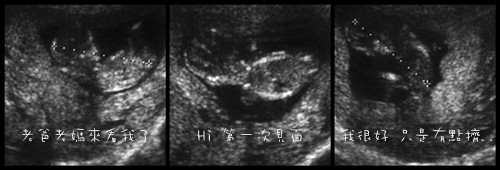

好吧!胎兒都這麼大了才第一次見面!

原來我已經三個月了,是從最後一次月經的第一天算起,是該公布的時候了;

還好醫生說大致都還不錯,而且長得很大 (有多大?!就5公分...醫生,這樣算大嗎?)